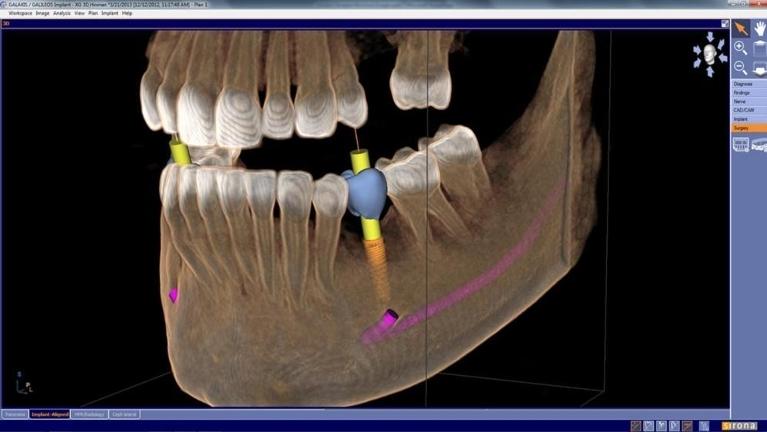

3D Xray & Treatment Planning Technology

3D x-rays, also known as Cone Beam or CBCT, allow our dental team to generate 3-dimensional images to assess your teeth, bone, soft tissues and nerve pathways all in a single scan. On site, our team can then precisely treatment plan and document every step of the journey digitally.